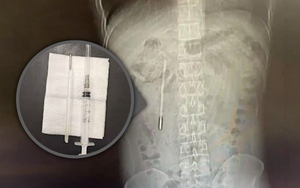

Đi viện vì đau dạ dày, người đàn ông bất ngờ phát hiện chiếc nhiệt kế thủy ngân nằm trong bụng suốt hai mươi năm

Đời sống 2026-04-15T21:20:00Một người đàn ông 32 tuổi đến bệnh viện do đau dạ dày đã vô cùng sửng sốt khi phát hiện một chiếc nhiệt kế thủy ngân mà anh từng vô tình nuốt vào hồi mười hai tuổi vẫn còn nằm nguyên vẹn bên trong cơ thể mình.